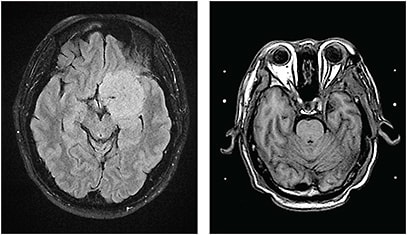

Visual field examination showed a near full field OD, but a severely compromised field was noted OS (Figure 3, next page). Compressive optic neuropathy was suspected. Brain MRI revealed a left skull base meningioma 4.7 x 4.2 cm in size (Figure 4, left).

Figure 4. A large homogenous enhancing, extra-axial meningioma in the left suprasellar and parasellar region, with dural tail sign, causing encasement and focal narrowing of the left terminal internal carotid artery, proximal anterior cerebral artery and middle cerebral artery. Follow-up MRI (right) showed that residual meningioma was controlled by subsequent Gamma Knife radiosurgery.

The residual meningioma was controlled by Gamma Knife radiosurgery (Figure 4, right). The patient’s BCVA improved to 16/20 postoperatively. No recurrence was noted over one year of follow-up.